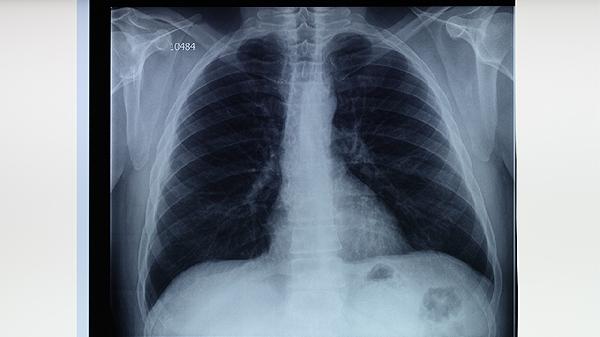

胸部X线检查可发现肺结核的典型影像学表现,如上肺野浸润影、空洞形成、纤维条索影等。该检查具有辐射量低、便捷经济的优势,是肺结核筛查的常规手段。但需注意某些不典型病例可能与其他肺部疾病影像表现重叠,需结合其他检查综合判断。